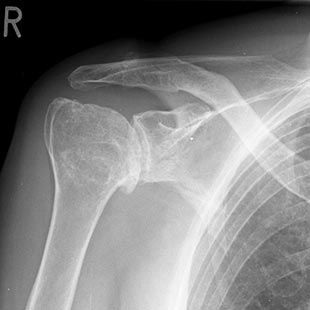

Unter einer Omarthrose versteht man den Gelenkverschleiß im Schultergelenk im Sinne eines Defektes der Knorpelstrukturen der gelenkbildenden Anteile von Humeruskopf und Schultergelenkspfanne.

SchultergelenksarthroseDie Erstbehandlung besteht in konservativen Maßnahmen wie Krankengymnastik, manueller Therapie, Kortisoninjektionen in das Gelenk und schmerzstillenden Medikamenten (NSAR). Um den Knorpelverschleiß zu minimieren können auch Injektionen mit Hyaluronsäurepräparaten („Spritzenkur“) erfolgen. Diese wirken dem zunehmenden Gelenkverschleiß entgehen.

Kleinere Areale eines Gelenkverschleißes können über eine Anfrischung (= Mikrofrakturierung) minimalinvasiv (arthroskopisch) adressiert werden, um die Neubildung von Gelenkknorpel anzuregen. Bei einem größeren, aber lokalisierten Knorpelschaden kann dieser mit einem Teilersatz (Hemicap) behandelt werden. Ist die Gelenkfläche komplett zerstört, sollte ein Gelenkersatz erfolgen.

Eine Gelenkspiegelung (Arthroskopie) der Schulter kann allerdings auch bei fortgeschrittenem Gelenkverschleiß durchaus die Beweglichkeit des Gelenkes und die Patientenzufriedenheit vergrößern bei deutlicher Verringerung der Schmerzhaftigkeit. Im Rahmen eines „comprehensive arthroscopic management“ (CAM-Prozedere) werden hierbei im Gelenk vorhandene freie Gelenkkörper entfernt, knöcherne Anbauten abgetragen, Knorpelränder geglättet, die entzündete Gelenksinnenhaut reseziert, die Kapsel eingeschnitten und der Axillarisnerv bei Bedarf freigelegt und vom Druck befreit. Bis zur ggf. dann nötigen Implantation einer Endoprothese können dadurch einige Jahre für den Patienten gewonnen werden, bei deutlicher Verbesserung des Lebenswertes.